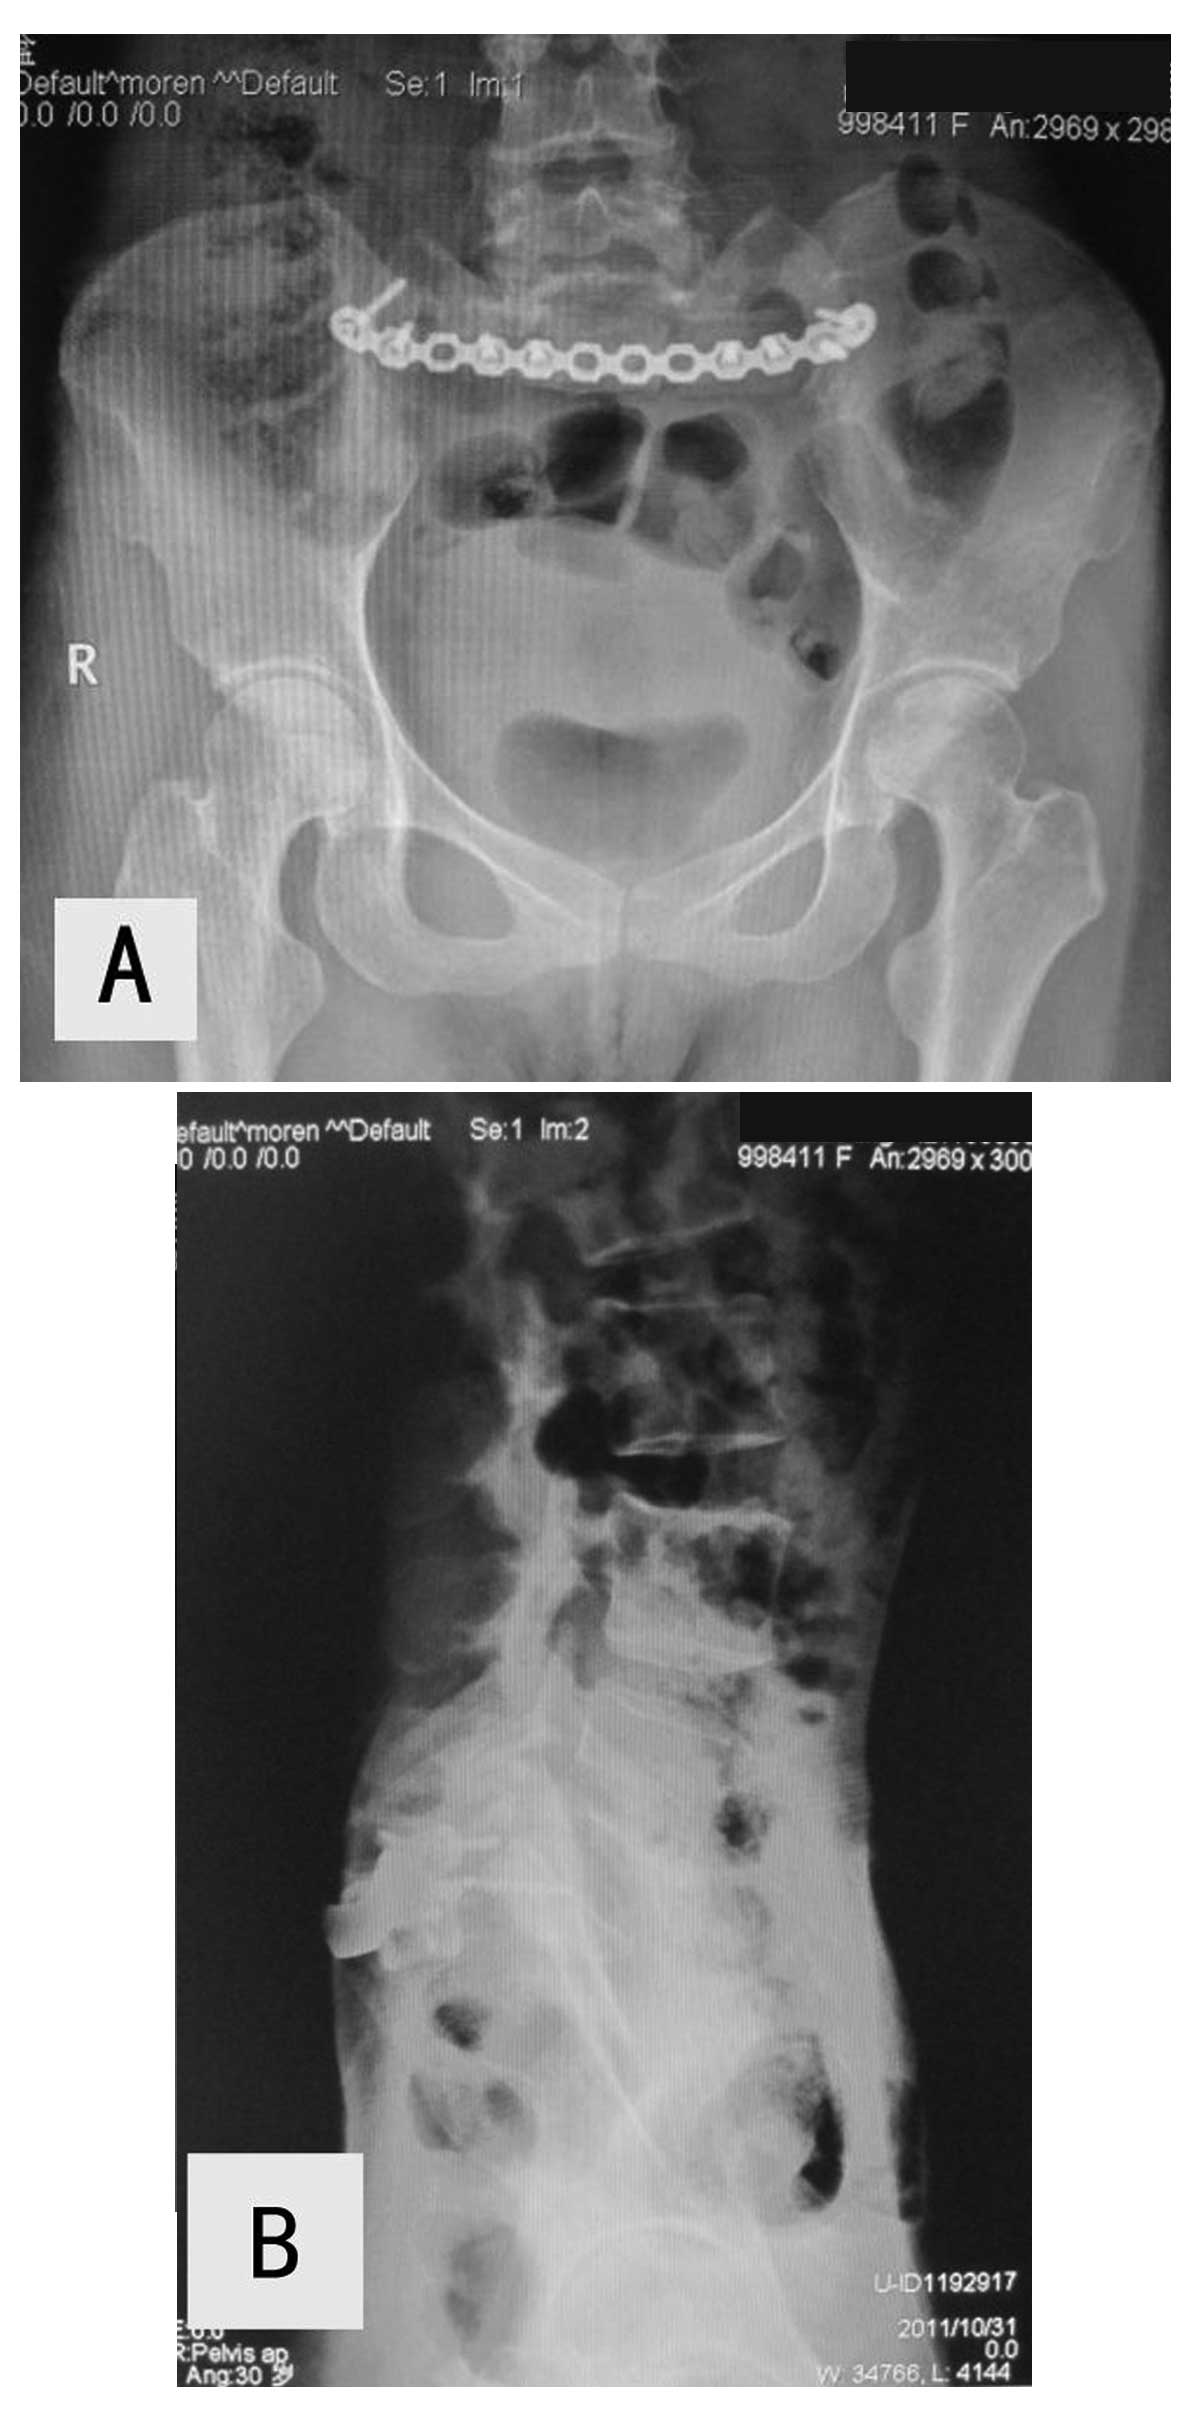

X Ray Multiple Part Of Child S Body Multiple Disease Stroke Brain Tumor Rheumatoid Arthritis Sinusitis Gouty Arthritis Etc Skull Chest Lung Heart Spine Arm Hand